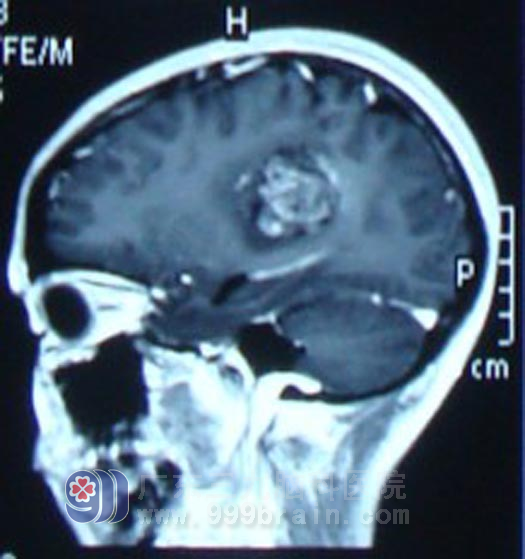

4月12日,阿玲来到广东三九脑科医院神经外科就诊,当时,阿玲言语表达能力已经明显下降,查头颅MRI示左侧顶叶占位性病变。很快,医生为阿玲安排了手术治疗,由于肿瘤与脑组织之间粘连紧密,手术无法做到全切除肿瘤。术后病理检查显示阿玲患的是胶质母细胞瘤IV级,恶性程度非常高,极易复发。http://www.999brain.com/

治疗前